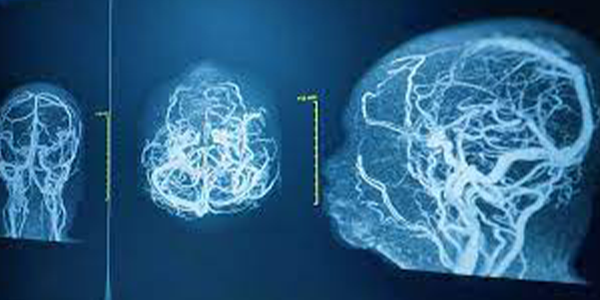

Serebral Anjiyografi ve AVM

Arteriovenöz malformasyon (AVM), beyin damarları arasında anormal bağlantılardır. AVM'ler, beyin kanamasına veya diğer nörolojik problemlere neden olabilir. Serebral anjiyografi, AVM'leri teşhis etmek ve tedavi planlamak için kullanılır.

Serebral Anjiyografi ve Anevrizma

Anevrizma, beyin damarlarında balon gibi bir şişkinliktir. Anevrizmalar, yırtılarak beyin kanamasına neden olabilir. Serebral anjiyografi, anevrizmaları tespit etmek ve boyutlarını, şekillerini ve yerleşimlerini değerlendirmek için kullanılan en iyi yöntemdir.